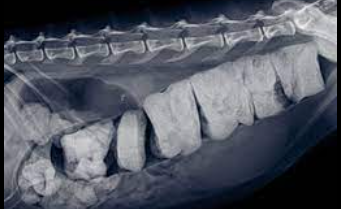

고양이 변비

- 거대결장 등에 의한 변비

- 골반골절